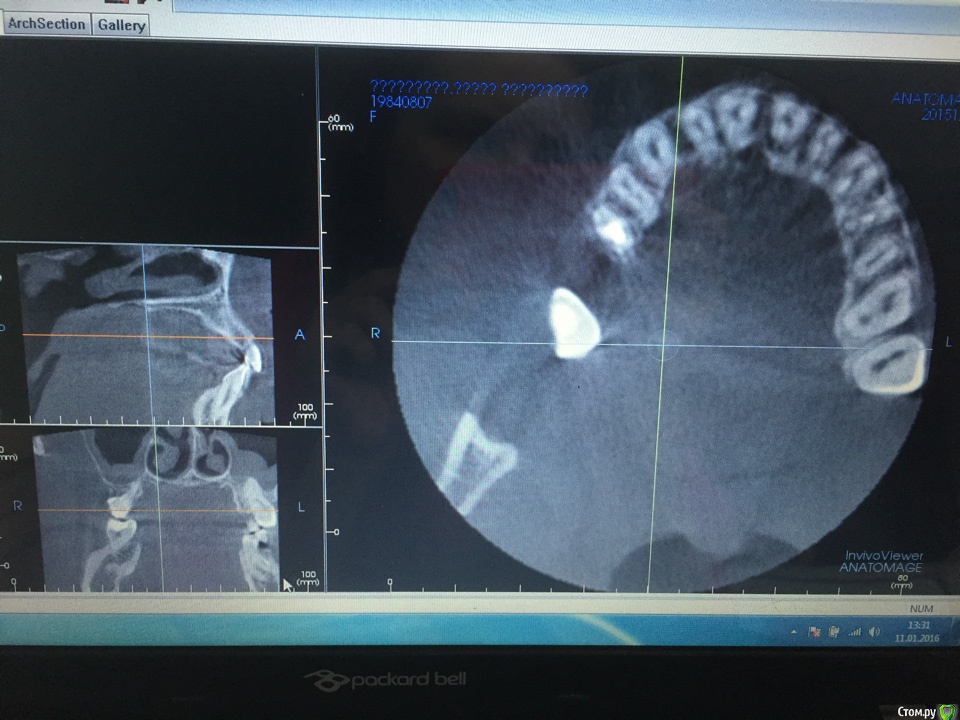

malesha Опубликовано 11 января, 2016 Поделиться Опубликовано 11 января, 2016 Добрый день! ситуация такая, около года небольшой отек щеки с правой стороны, в области носогубной складки, время от времени то больше, то меньше, даже не пойму от чего .... была у многих врачей, удалила уже несколько зубов- и вот в последний раз удалив семерку настало улучшение, но не прошло и двух недель опять появился отек. десны с правой стороны воспалены. Врач настаивает, что у меня гайморит, но кроме как в нос и отека других симптомов нет. Подскажите, что показывает снимок? к каким врачам обращаться? нужны ли дополнительные исследования кроме кт для постановки диагноза гайморит Ссылка на комментарий

IvanK Опубликовано 11 января, 2016 Поделиться Опубликовано 11 января, 2016 ЗдравствуйтеСрез не информативен Ссылка на комментарий